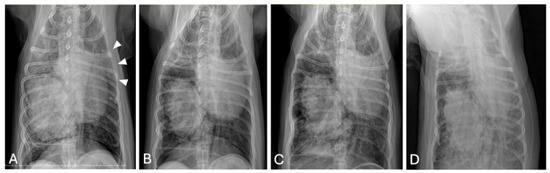

Computed Tomographic and Ultrasonographic Features in Three Dogs with Infected Uterus Masculinus and Concurrent Genital Neoplasia

Uterus masculinus is a rare disorder of sexual development in males, characterized by the presence of tubular female genitalia. Diagnostic imaging reports of infected uterus masculinus are limited. We describe the ultrasonographic and computed tomographic findings in three dogs, all presenting with abdominal distension, pain, and systemic infection. Imaging consistently revealed a fluid-filled, bicornuate structure arising from the prostate. In two dogs, the horns extended through the inguinal rings to the scrotal testes; in the third, with a prior left orchiectomy, both horns were intra-abdominal, the right ending in a peritoneal mass. Surgery and histopathology confirmed infected uterus masculinus, with Escherichia coli isolated from urine in all dogs and from the structure in two. Two dogs had Leydig cell tumors, one with concurrent uterine neoplasia; the third had an ovarian or ovotesticular granulosa cell tumor. Although rare, infected uterus masculinus is potentially life-threatening and should be considered in male dogs with abdominal pain, distension, or systemic infection. This is the first case series describing combined ultrasonographic and tomographic features of infected uterus masculinus, including novel findings such as cervix-like mural narrowing and fluid–fluid levels. It is also the first imaging description of an ovarian or ovotesticular tumor in a dog with uterus masculinus. Full article

Figure 1